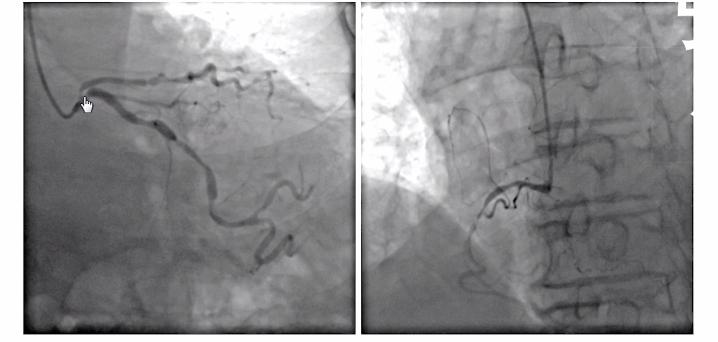

下图是王老汉的冠脉造影,可以看到老人的左冠状动脉,不管是回旋支还是前降支都存在着严重的病变,尤其是该病人的左主干非常短,前降支开口又是一个99%的狭窄,几乎是要闭塞的。

患者的右冠状动脉,又是个广泛的弥漫性病变,还有一个次全闭塞的一个病变。